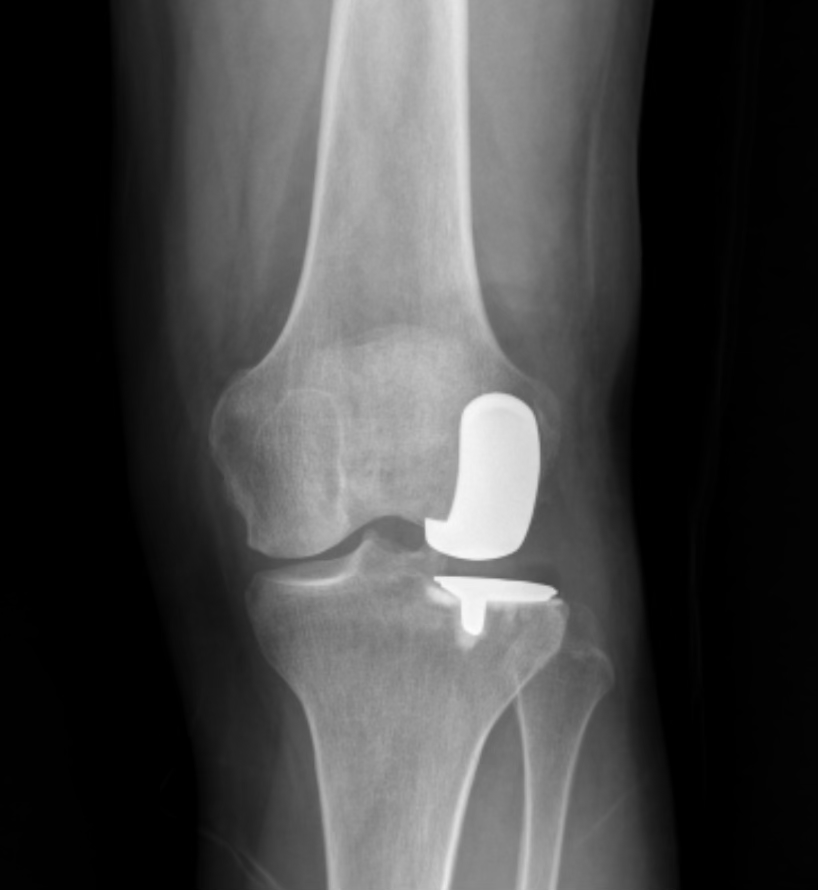

If you’ve been reading this newsletter for even a little while, you’ll know that the Zagori race has become an annual tradition for me. I first raced the 10km on a lark on zero training (I was pretty much only rowing back then), and then moved up in distance to the 44km event they had for many years. I had hoped to run the 60km in 2025. But my left knee—specifically one of the three compartments of my left knee—had other plans. I dialed back to the 21km event last summer, and, ten days later, had a partial knee replacement.

I am almost at the six-month mark now—six months after surgery. My left knee still has some swelling in it, which my orthopedist’s practice assures me is normal, and I can tell by just looking that my left quad is a bit smaller than my right. But the knee does pretty much everything I ask of it. Skiing of all kinds (xc, skate, uphill, downhill), rowing (indoors now. I do not have a death wish.), cycling (ditto), strength training, hiking. And running.

Why? Because of Lindsey Vonn. Sort of. As my friend the orthopedist explained to me before my decision to have surgery, I had Lindsey Vonn’s knee. Like her, I had two healthy knee compartments and one wrecked one. So, like her, I had surgery to replace not the whole knee, but just a part of it.1